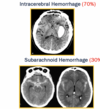

37

The vast majority of strokes (85%) are (ischemic/hemorrhagic)

The vast majority of strokes (85%) are **ischemic** * *Ischemic strokes involve embolic, thrombotic, lacunar*

38

Hemorrhagic strokes are caused by either [bleeding] or [bleeding]

Hemorrhagic strokes are caused by either **subarachnoid hemorrhage** or **intracerebral hemorrhage**